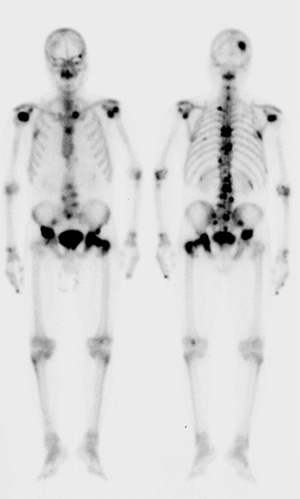

骨転移の核医学的診断と治療

Fdg Petによるがん骨転移の診断